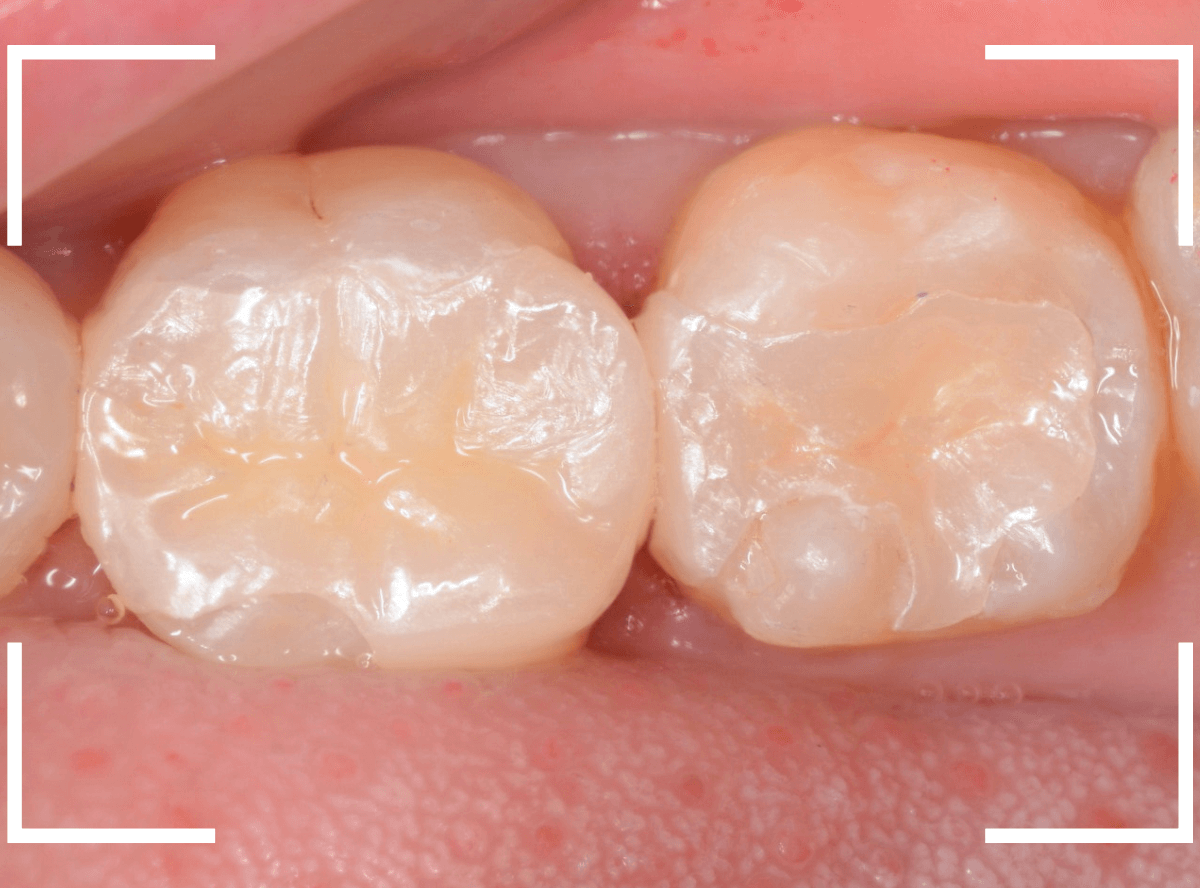

set後の写真です。

患者さんにも満足していただける仕上がりになりました。